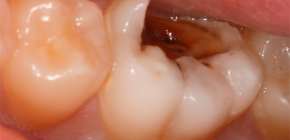

Quindi, se improvvisamente un dente relativamente piccolo e inquietante ha iniziato improvvisamente a "compiacerti" con dolore acuto e di lunga durata, allora è il momento di ricordarti - non puoi liberarti degli antidolorifici da solo, poiché è necessario un trattamento urgente. Il trattamento della pulpite è quasi sempre associato alla necessità di rimuovere la polpa dal dente, quindi sarebbe molto meglio curare la carie in una volta piuttosto che ottenere un dente morto senza un "nervo" dopo il trattamento.